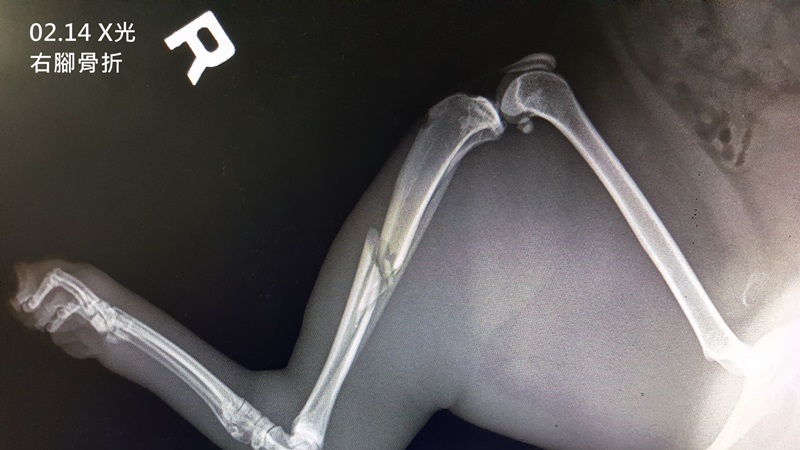

到了醫院的馬辣緊張到屎尿齊發,醫師進行檢查,他的右後腿骨折、並可能是蜂窩性組織炎使得整隻腿腫脹、尚未結紮,醫師於隔日將馬辣麻醉後進一步檢查,全套血檢白血球偏高、二合一檢查為陰性、x光檢查確定右後肢骨折,醫師先以抗生素治療感染,因骨折情況較為繁複,故轉院做進一步處理。

2月14日 進行全套血檢、二合一檢驗、X光、打長效抗生素、除蚤。